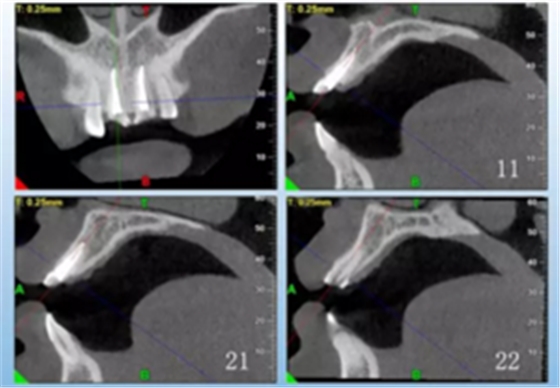

患者,女性,23岁,外伤导致上前牙折断3天。检查:中微笑 线;上颌右侧中切牙至左侧侧切牙残根,不松动,腭侧缺损达龈下5mm, 牙龈中等厚度,龈缘基本完好。CBCT显示:根长约11mm,牙根长轴与牙 槽突方向基本一致,唇侧骨板完好、厚度1.0mm,可用骨高度21mm。全身情况良好。

图3 术前CBCT